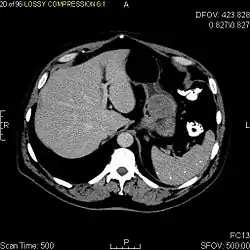

The purpose of radiologic imaging is to locate the lesion, evaluate for signs of invasion and detect metastasis. Features of GIST vary depending on tumor size and organ of origin. The diameter can range from a few millimeters to more than 30 cm. Larger tumors usually cause symptoms in contrast to those found incidentally which tend to be smaller and have better prognosis.[4][20] Large tumors tend to exhibit malignant behavior but small GISTs may also demonstrate clinically aggressive behavior.[21]

Barium fluoroscopic examinations and CT are commonly used to evaluate the patient with abdominal complaints. Barium swallow images show abnormalities in 80% of GIST cases.[21] However, some GISTs may be located entirely outside the lumen of the bowel and will not be appreciated with a barium swallow. Even in cases when the barium swallow is abnormal, an MRI or CT scan must follow since it is impossible to evaluate abdominal cavities and other abdominal organs with a barium swallow alone. In a CT scan, abnormalities may be seen in 87% of patients and it should be made with both oral and intravenous contrast.[21] Among imaging studies, MRI has the best tissue contrast, which aids in the identification of masses within the GI tract (intramural masses). Intravenous contrast material is needed to evaluate lesion vascularity.

Preferred imaging modalities in the evaluation of GISTs are CT and MRI,[23]: 20–21 and, in selected situations, endoscopic ultrasound. CT advantages include its ability to demonstrate evidence of nearby organ invasion, ascites, and metastases. The ability of an MRI to produce images in multiple planes is helpful in determining the bowel as the organ of origin (which is difficult when the tumor is very large), facilitating diagnosis.

Since GISTs arise from the bowel layer called muscularis propria (which is deeper to the mucosa and submucosa from a luminal perspective), small GIST imaging usually suggest a submucosal process or a mass within the bowel wall. In barium swallow studies, these GISTs most commonly present with smooth borders forming right or obtuse angles with the nearby bowel wall, as seen with any other intramural mass. The mucosal surface is usually intact except for areas of ulceration, which are generally present in 50% of GISTs. Ulcerations fill with barium causing a bull's eye or target lesion appearance. In contrast-enhanced CT, small GISTs are seen as smooth, sharply defined intramural masses with homogeneous attenuation.

Large GISTs

As the tumor grows it may project outside the bowel (exophytic growth) and/or inside the bowel (intraluminal growth), but they most commonly grow exophytically such that the bulk of the tumor projects into the abdominal cavity. If the tumor outstrips its blood supply, it can necrose internally, creating a central fluid-filled cavity with bleeding and cavitations that can eventually ulcerate and communicate into the lumen of the bowel. In that case, barium swallow may show an air, air-fluid levels or oral contrast media accumulation within these areas.[21][25] Mucosal ulcerations may also be present. In contrast-enhanced CT images, large GISTs appear as heterogeneous masses due to areas of living tumor cells surrounding bleeding, necrosis or cysts, which is radiographically seen as a peripheral enhancement pattern with a low attenuation center.[20] In MRI studies, the degree of necrosis and bleeding affects the signal intensity pattern. Areas of bleeding within the tumor will vary its signal intensity depending on how long ago the bleeding occurred. The solid portions of the tumor are typically low signal intensity on T1-weighted images, are high signal intensity on T2-weighted images and enhanced after administration of gadolinium. Signal-intensity voids are present if there is gas within areas of necrotic tumor.[22][26][27]

Features of malignancy

Malignancy is characterized by local invasion and metastases, usually to the liver, omentum and peritoneum. However, cases of metastases to bone, pleura, lungs and retroperitoneum have been seen. In distinction to gastric adenocarcinoma or gastric/small bowel lymphoma, malignant lymphadenopathy (swollen lymph nodes) is uncommon (<10%) and thus imaging usually shows absence of lymph node enlargement.[20] If metastases are not present, other radiologic features suggesting malignancy include: size (>5 cm), heterogeneous enhancement after contrast administration, and ulcerations.[4][20][28] Also, overtly malignant behavior (in distinction to malignant potential of lesser degree) is less commonly seen in gastric tumors, with a ratio of behaviorally benign to overtly malignant of 3-5:1.[4] Even if radiographic malignant features are present, these findings may also represent other tumors and definitive diagnosis must be made immunochemically.